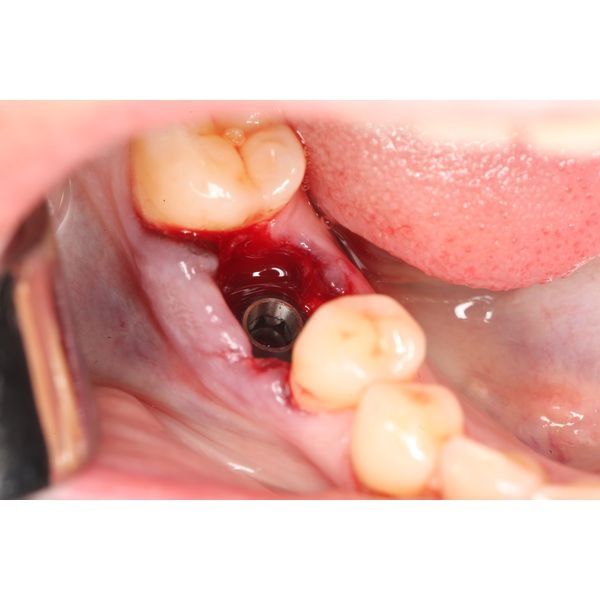

- установили дентальный имплантат и проверили его стабильность;

- установили формирователь десневой манжеты;